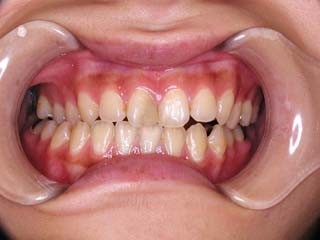

主訴:上の歯が出ている

診断名:顎関節症、下顎左右5欠損を伴う骨格性上顎前突

年齢:35歳

使用した主な装置名:TPB、マルチブラケット装置

抜歯/非抜歯および抜歯部位:非抜歯

治療期間:動的処置2年、経過観察3年

費用の目安:保険適応 自己負担金として30~50万

リスク、副作用:外科手術によるリスク、マルチブラケット治療に伴う歯根吸収など偶発症が発生するリスクがある。

強い骨格性の上顎前突が見られます。しばしば、口腔内所見では骨格のズレを歯の補償的な傾斜などでカムフラージュさせているため、あまり大したことのないズレにしか見えない事があります。また、上顎前突の場合は、下顎が関節の位置で知らず知らずのうちに前方へ大きく偏位させて噛んでいる事が多いです。このような場合は、咬合器に装着してみて初めて、治療方針が見えてくるかもしれません。どのような不正咬合であれ、大きなズレに対しては、外科的に骨のズレを改善する治療が理にかなっています。前後のズレ、垂直のズレと条件が重なってきた場合、より外科矯正での改善が望ましいでしょう。

一般的な外科矯正治療の流れは、術前矯正・外科矯正・術後矯正・保定治療と移行します。術後矯正では、手術後に僅かに見られる後戻りに対する処置や、刻々と変化する額関節の環境に対応して調節を続けます。特に大きな問題が無ければ6か月程度で保定治療に移行します。